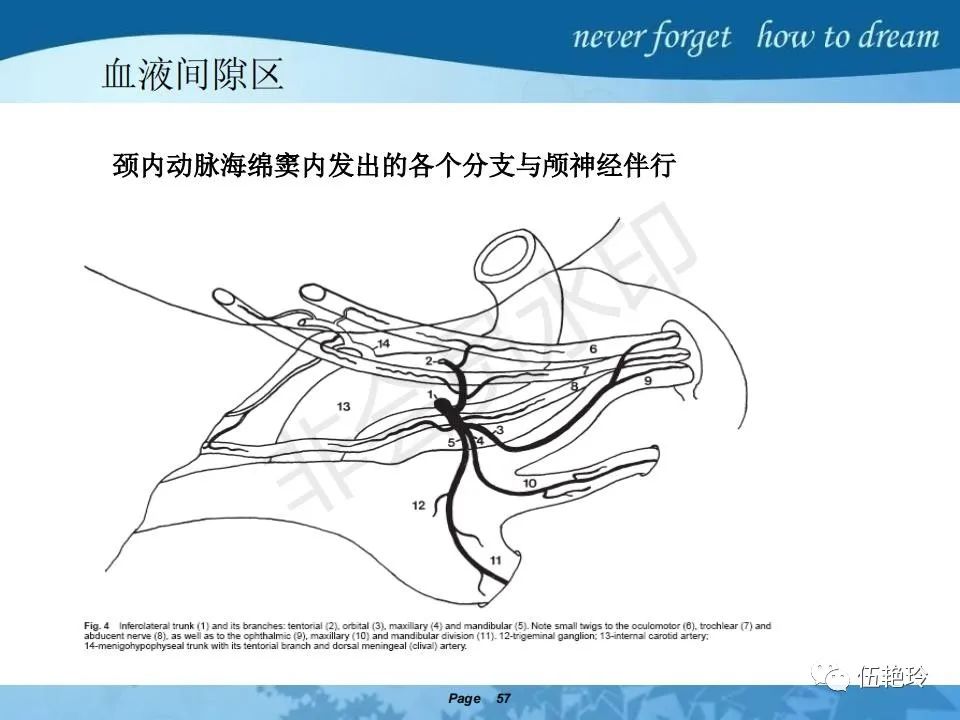

海绵窦区的解剖结构与鼻咽癌侵犯